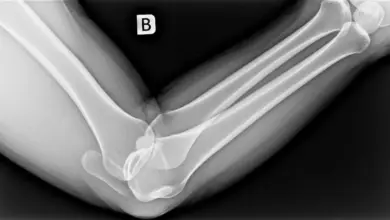

- Radiografia: identifica corpos livres calcificados e sinais de artrose.